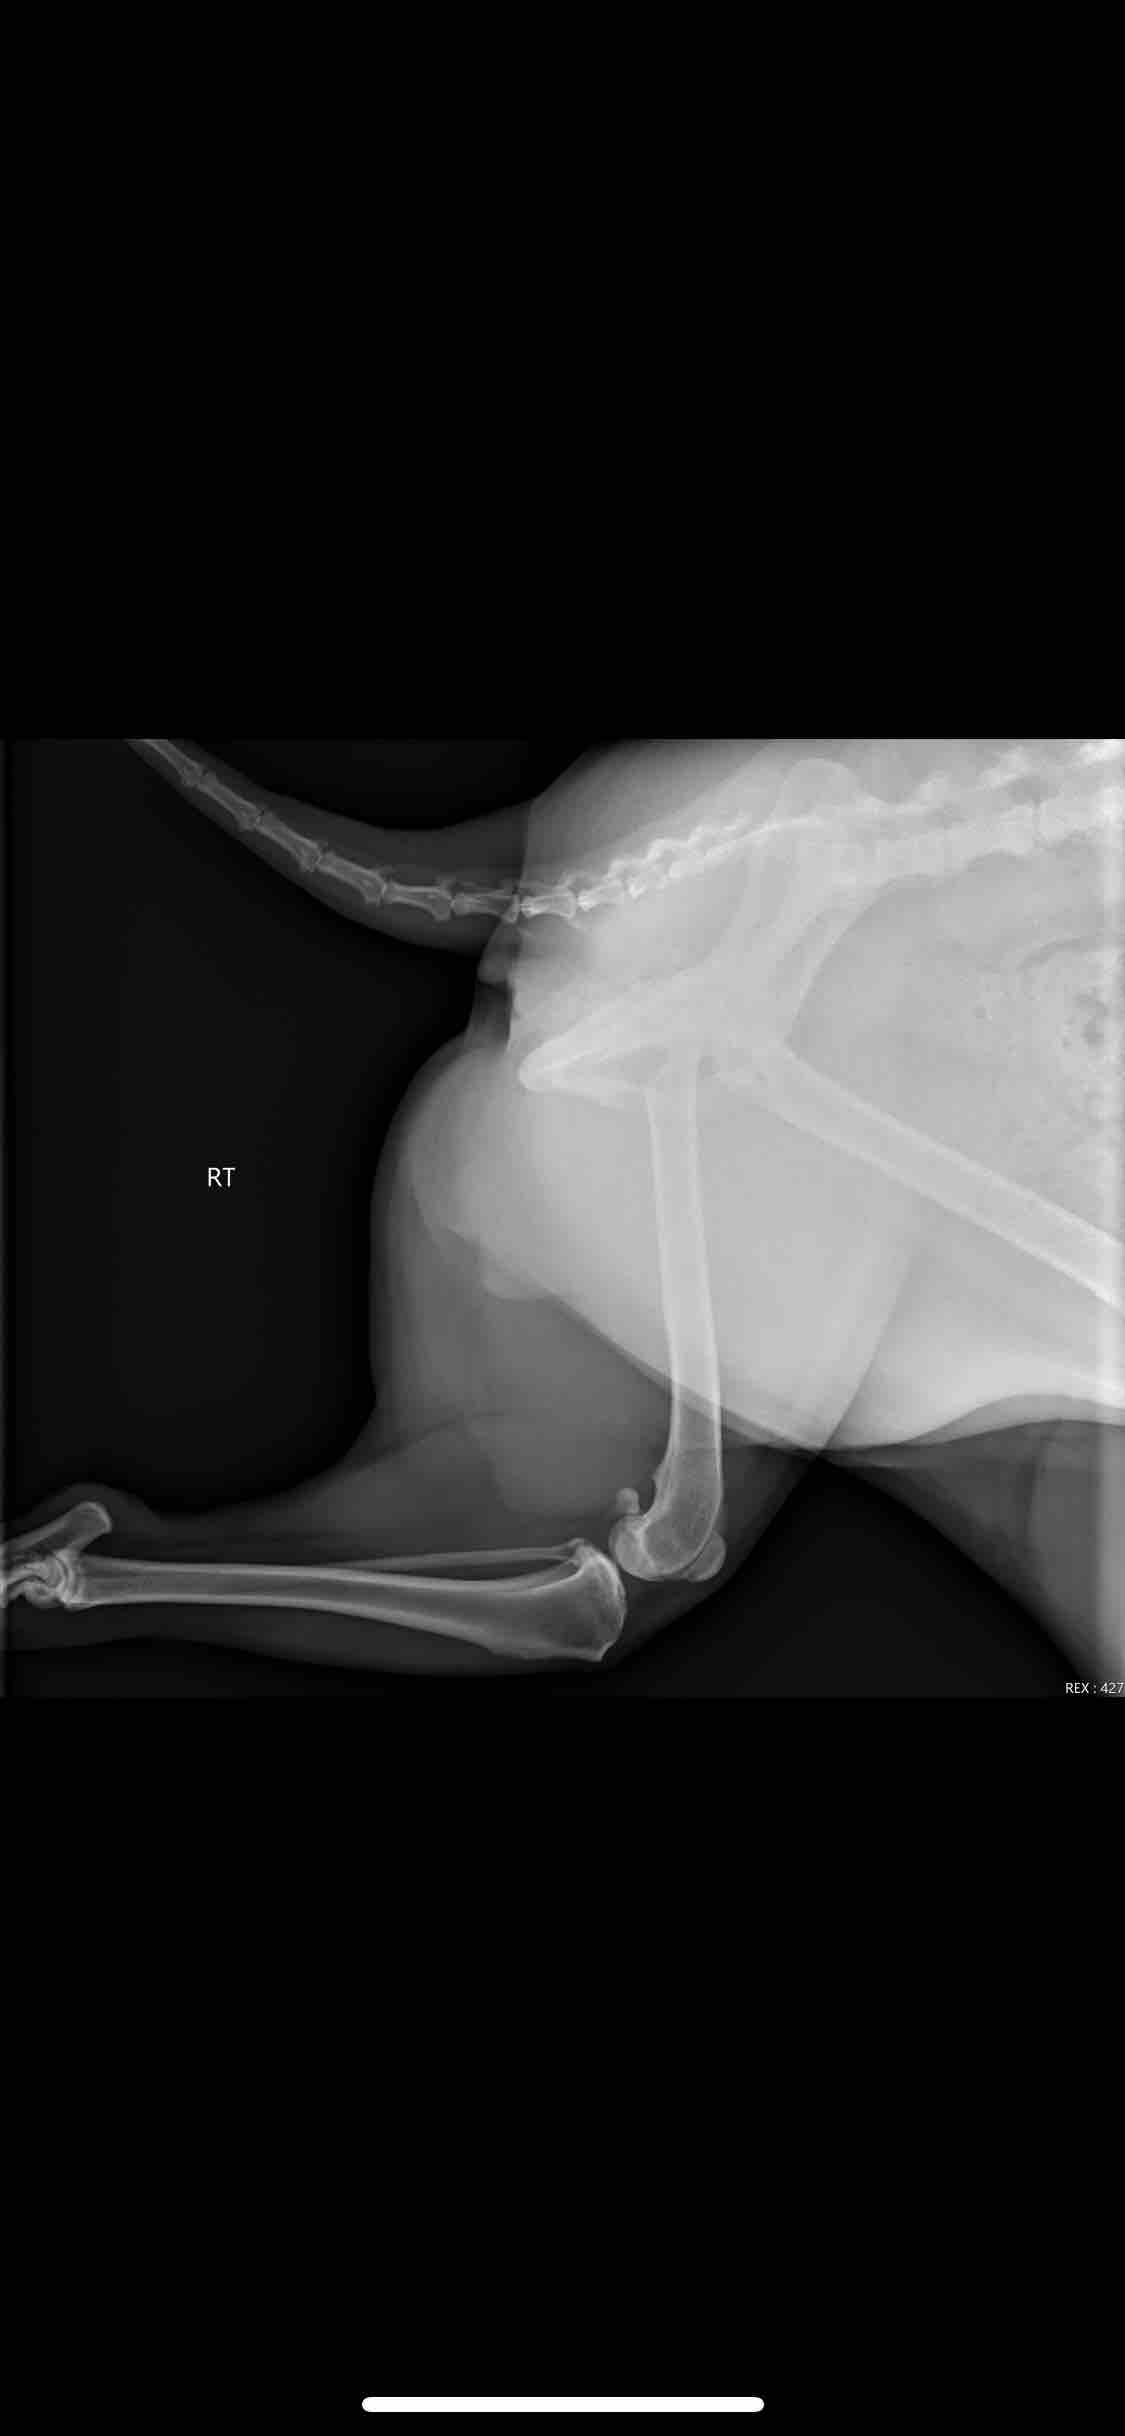

Hey guys, my name is Natasha and for those of you that know me, know that Nala is my absolute best friend and I would do anything for her and her well-being. That being said, I am in a bit of a rough spot as she was recently diagnosed with a torn ACL. My baby girl has been limping since February, where they initially noticed some inflammation on her meniscus based on radiographs done and prescribed rest and anti-inflammatory. Unfortunately, I did not see improvement as she kept limping on and off, and more recently (the past 2 and a half weeks or so) she has not put any weight on the back right leg. So I took her for a recheck about 2 weeks ago, to which they referred me to an Orthopedic Specialist. The specialist was able to confirm that it indeed is an ACL tear and she needs surgical intervention to repair it. Nala has been in pain, and it absolutely breaks my heart so see her walking the way she is, unable to bear weight on her back leg and not the same spunky, hyper girl she always is. I ask that you guys please share this post with everyone you know in hopes of reaching the goal for her surgery. I appreciate and thank everyone in advance for their contribution whether it be in sharing the post or donating. I will also attach a link to where you can see her limping :(